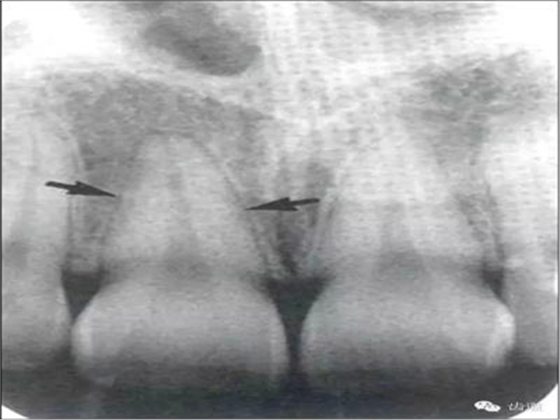

牙頸部Burnout征象:有時(shí)因投照技術(shù)問(wèn)題而造成牙頸部近中或遠(yuǎn)中呈低密度影像,位于牙釉質(zhì)和牙槽嵴頂之間。